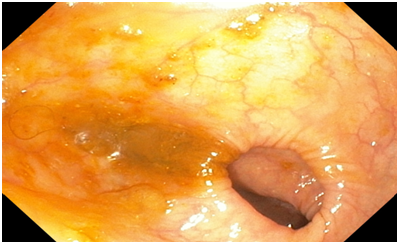

Colonoscopy. The colonoscope was passed all the way down to the ascending colon (distal part). The ascending colon contained circumferential fungating necrotic mass lesion extending all the way down to the caecum. The mass was friable, bled easily both spontaneously and with contact. Multiple biopsy samples were taken from the mass. There was some degree of luminal narrowing as well. The rest of the examined colon all appeared normal. No diverticulum or polyp seen. No observable synchronous tumour seen. Endoscopic Diagnosis was Right-sided colonic adenocarcinoma.

Figure 1 An Endoscopic image of the Hepatic flexure showing the tumour mass.

Figure 2 An Endoscopic image of the Ascending colon showing the tumour extending all the way to the cecum.